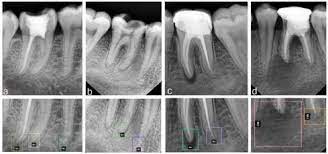

Periapikal: Pemeriksaan Kecil dengan Informasi Besar!

Anggelia Gita Tiyananda A.Md.Kes.(Rad)

Halo, Sobat Jo! 👋  Yuk kita mengenal apa itu Rontgen Gigi Periapikal! 🦷 Periapikal: Pemer...

Rontgen Gigi Periapikal

Biaya Pemeriksaan Foto Rontgen gigi Periapikal

Rp 105.000